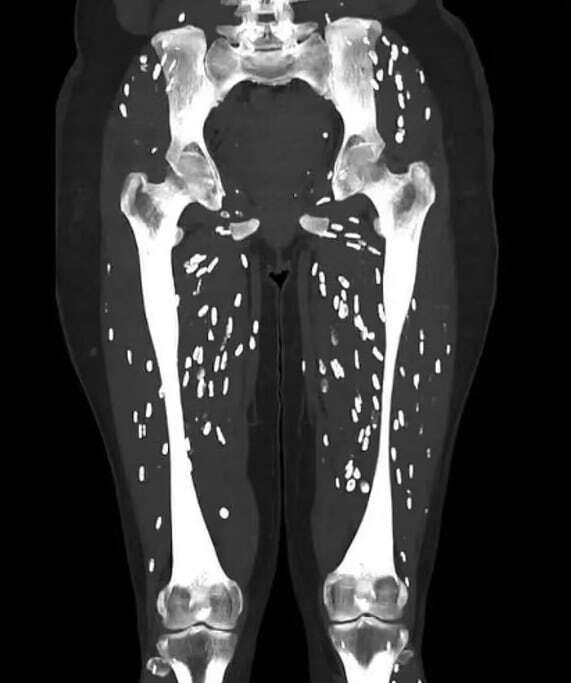

28일(현지시각) 데일리메일에 따르면 미국 플로리다 대학교 의대병원 응급실 의사인 샘 갈리 박사는 지난 25일 X(옛 트위터)에 ‘낭미충증’이라는 기생충에 감염된 환자의 다리 CT 사진을 게시했다.

갈리 박사가 공개한 CT 사진에서는 다리로 옮겨진 낭종의 모습을 선명하게 볼 수 있었다. 해당 환자는 대퇴골을 시작으로 무릎 관절 아래까지 유충을 담고 있었고 수많은 낭종이 퍼져 있었다.

갈리 박사는 “유충은 장을 빠져나와 혈류로 전신 어느 곳에나 퍼진다”며 “뇌, 눈, 피하조직, 골격근이 가장 흔한 목적지”라고 설명했다. 이어 “낭미충증은 대변을 통해서도 전염될 수 있다”면서 “감염된 사람이 화장실에 다녀온 후 제대로 손을 씻지 않은 채 여러 사람과 음식을 함께 먹거나 배설물로 오염된 물을 통해 전염된다”고 했다.